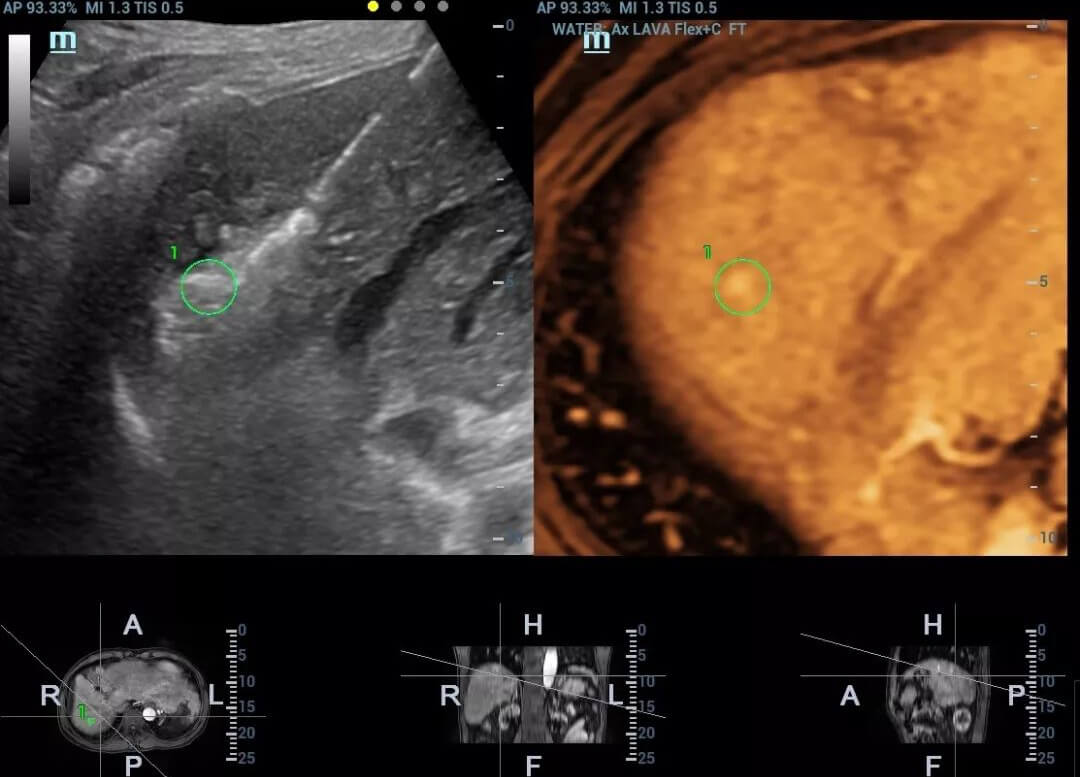

A typical clinical application scenario comes to the ultrasound-guided radiofrequency ablation when pure ultrasound fails to guide insertion of the needle accurately. In such case, based on lesion's target marker in both MRI and ultrasound images, Fusion can guide the needle tip to the lesion location precisely, increasing the accuracy of positioning e?ectively.

Besides Respiration Compensation, the quad mode has also been highly validated and welcomed by clinicians. It provides separate fusion imaging of CT/MRI with tissue and contrast enhanced ultrasound images, making it easy to visualize lesions on different types of images. This real-time and comprehensive multiple modality displaying renders better diagnostic confidence.?